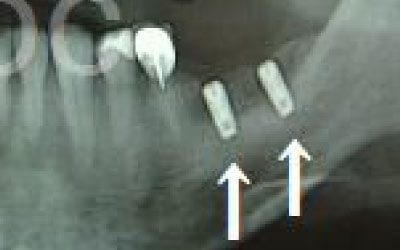

CTを使うと、骨や歯の状態を立体的に確認でき、正確な距離も測定できます。

骨の厚さや傾き、神経の位置などを事前に詳しく把握することで、安全にインプラント治療を行うことができるのです。

しかし、当院では事前にCT撮影を行い、神経までの距離を三次元的に正確に把握した上で治療計画を立てるため、リスクをしっかり回避できます。

さらに、骨を削りすぎないようにするための専用のストッパーも導入しており、安全性には十分に配慮しています。